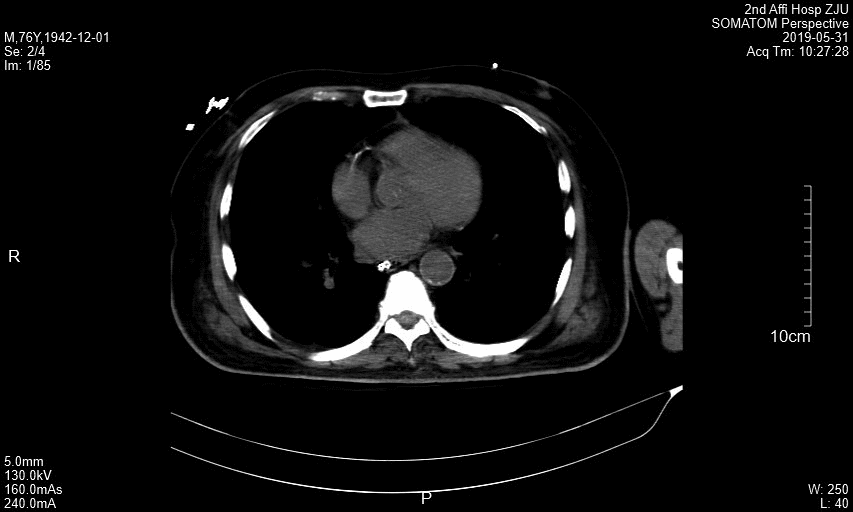

附图1 患者横断面CT图